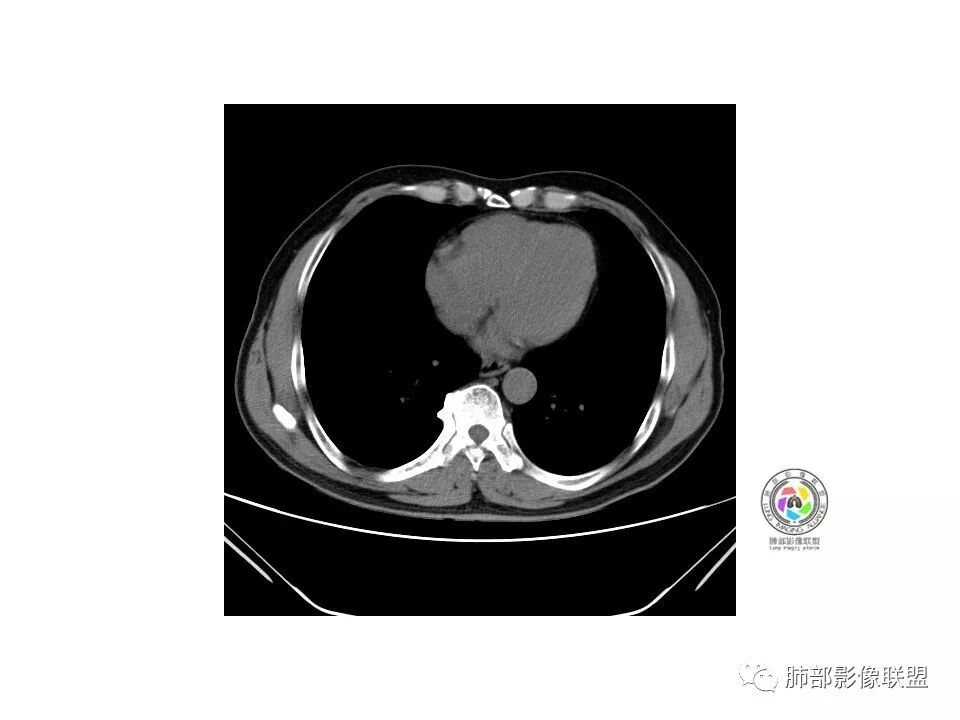

右肺下叶见边界清晰混合磨玻璃密度影,目测内见实性结节小于5mm,有浅分叶,前缘小叶间隔阻挡,月牙铲?胸膜牵拉,老年患者,MIA可能,鉴别炎性病变,抗炎后复查

患者老年男性,以咳嗽 、咳痰3天就诊,胸CT:右肺下叶前基底段mGGO,内可见血管形态改变,细支气管扩张,病灶边界清,边缘可见月牙铲。考虑恶性,腺癌?但建议先抗炎治疗后复查

患者老年男性,咳嗽  咳痰3天就诊。胸部CT:右肺下叶前基底段混合磨玻璃结节,边缘清楚,可见毛刺、胸膜牵拉、血管集束、月牙铲征象。综合考虑微浸润腺癌可能大。

右肺下叶前基底段混合磨玻璃结节,边界清,浅分叶,胸膜牵拉,月牙铲,血管进入,考虑:微浸润腺癌可能性大,抗炎后复查。

老年男性,咳嗽、咳痰3天。胸部CT:右肺下叶前基底段mGGN,边缘清楚,内可见不规则实性成分,病灶可见空泡、毛刺、胸膜牵拉、血管集束征象。考虑MIA可能大,抗炎2W后复查。

老年男性,右下肺前基底段混合GGN,边缘清晰,月牙铲,叶间胸膜牵拉,有轻度收缩力。结合病史抗炎2-3周后复查,消失考虑炎症,变化不大为腺癌。本例总体支持腺癌

老年男性,咳嗽3天,右肺下叶前基底段混合磨玻璃结节,形态不规整,相邻胸膜凹陷,可见血管影,考虑腺癌可能性大,不除外炎症可能,建议抗炎1~2周,1个月复查胸部CT。

老年男性,右肺下叶前基底段斜裂旁可见单个混合型磨玻璃结节mGGN,边缘清,内部结构紊乱,进入的血管增粗,支气管关系不好判断,斜裂侧可见牵拉,常规考虑微侵腺癌MIA,建议先抗炎后复查及手术干预。

老年男性,咳嗽咳痰3天。MGGN,边缘见月牙铲、胸膜牵拉,血管移动联通?冠状位隐约可见支气管穿行,考虑MIA,重建冠位可见结节比较靠近叶裂,可积极手术处理。

老年男性,右S8混合磨玻璃结节,边缘尚清晰,局部凹陷,叶间胸膜牵拉,考虑MIA可能大,建议抗炎治疗10天,6-8周后复查

患者老年男性,右下肺前基底段靠近胸膜侧可见一个mGGO结节,边缘清淅,可见分叶征及月牙铲,小结节病灶胸膜牵拉明显,首先考虑MIA可能性大。

右肺下叶前基底段mGGN,边界清晰,内部结构杂乱,见网格空泡感,月牙铲,浅分叶及胸膜牵拉,倾向MIA。